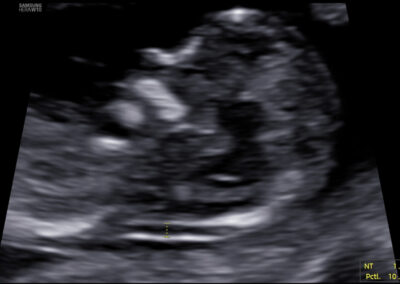

On-line teoretický kurz (e-teaching) o vyšetření v 11.-14. týdnu těhotenství na www.fetalmedicine.com (část Fetal Medicine Foundation- volba Training & Certification v menu na horní liště, následně položka Certificates of competence – volba modré položky Measurement of nuchal translucency) Elektronické zaslání tří snímků ze správného vyšetření NT dle FMF protokolu (viz protokol pro vyšetření níže), snímky mohou zobrazovat měření normální i abnormální hodnoty NT – nutná je správná pozice značek měření